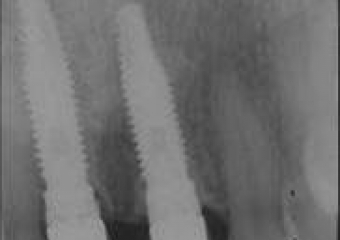

Raio X final

Controle do caso, realizada em janeiro de 2012.